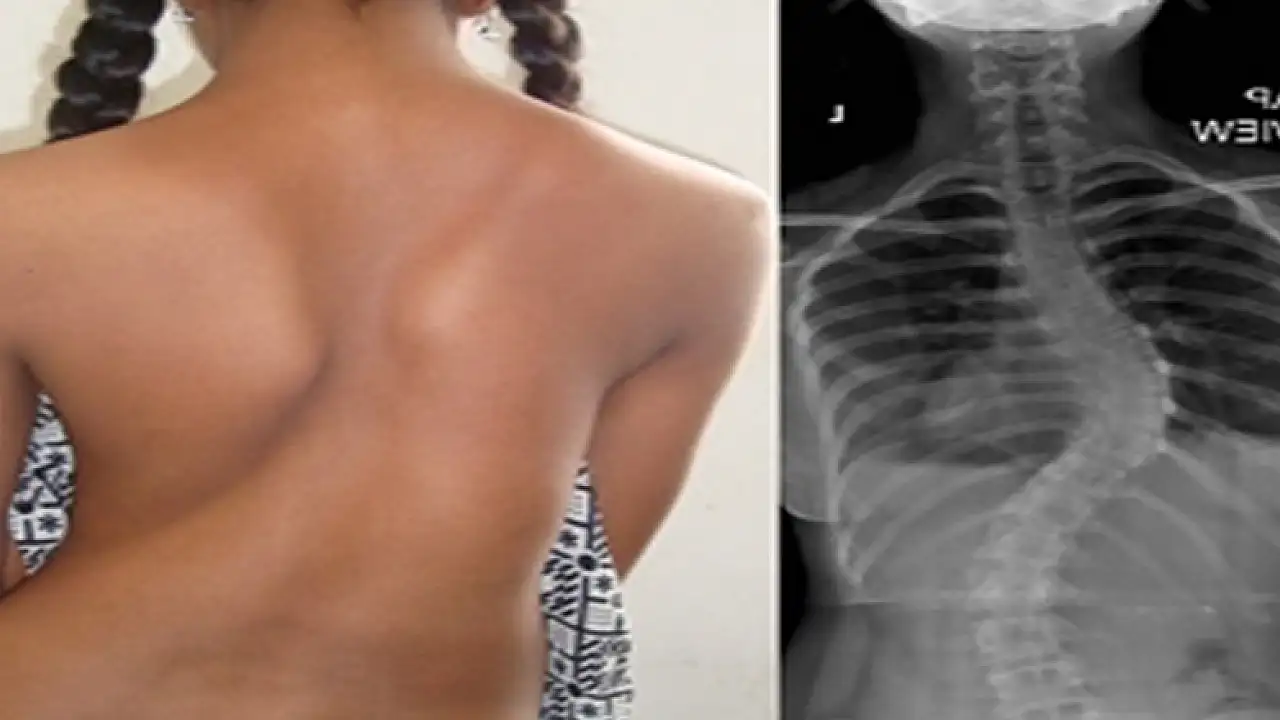

Skolyozun, tamamen düz olması gereken omurganın sağa veya sola doğru eğilmesiyle ortaya çıktığını belirten VM Medical Park Samsun Hastanesi Ortopedi ve Travmatoloji Kliniğinden Prof. Dr. Turgut Nedim Karaismailoğlu, “Skolyoz belin veya sırtın yana doğru eğriliğine denir. Skolyoz toplumda yüzde 4-5 oranında gözükür. Türkiye'de şu anda 2,5 milyon civarında skolyoz hastası mevcuttur. Skolyoz hastalığı doğuştan gelebildiği gibi her yaşta ortaya çıkabilir” dedi.

Çocuklarda en sık 10 yaşlarından sonra görüldüğünü belirten Prof. Dr. Turgut Nedim Karaismailoğlu, “Kızlarda görülme oranı 8-10 kat daha fazladır. Hiç bir şikayeti olmayan çocuğun bile 10 yaşından sonra skolyoz olabilme ihtimali vardır. Büyümenin hızlanması ile eğrilikteki artma miktarı hızlanır. Bu artış 16-17 yaşına kadar devam eder. Skolyozun yüzde 80'inin nedeni bilinmemektedir. Bazı ailelerde skolyoza daha sık rastlanmaktadır. Bu nedenle skolyoz hastası olan aileler daha dikkatli olmalıdır” diye konuştu.